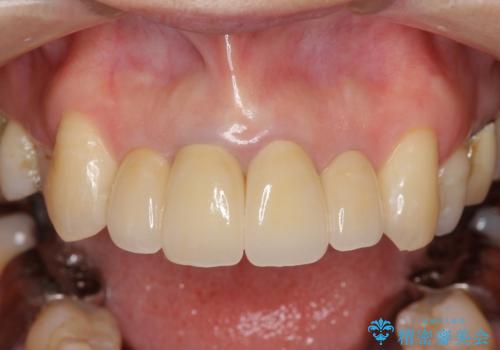

劣化したクラウンを除去し、再発した虫歯を徹底的に除去したのち根管治療・ファイバーコア築盛を行いジルコニアクラウン製作へと移ります。

- 52万円(仮歯・ファイバーコア・ジルコニアクラウン×4)費用は治療当時の料金となります

歯ぐきの位置は経年的に変化することがあります。その際にもジルコニアクラウンはクラウンの際が黒くなく目立ちにくく審美的なクラウンと言えます。